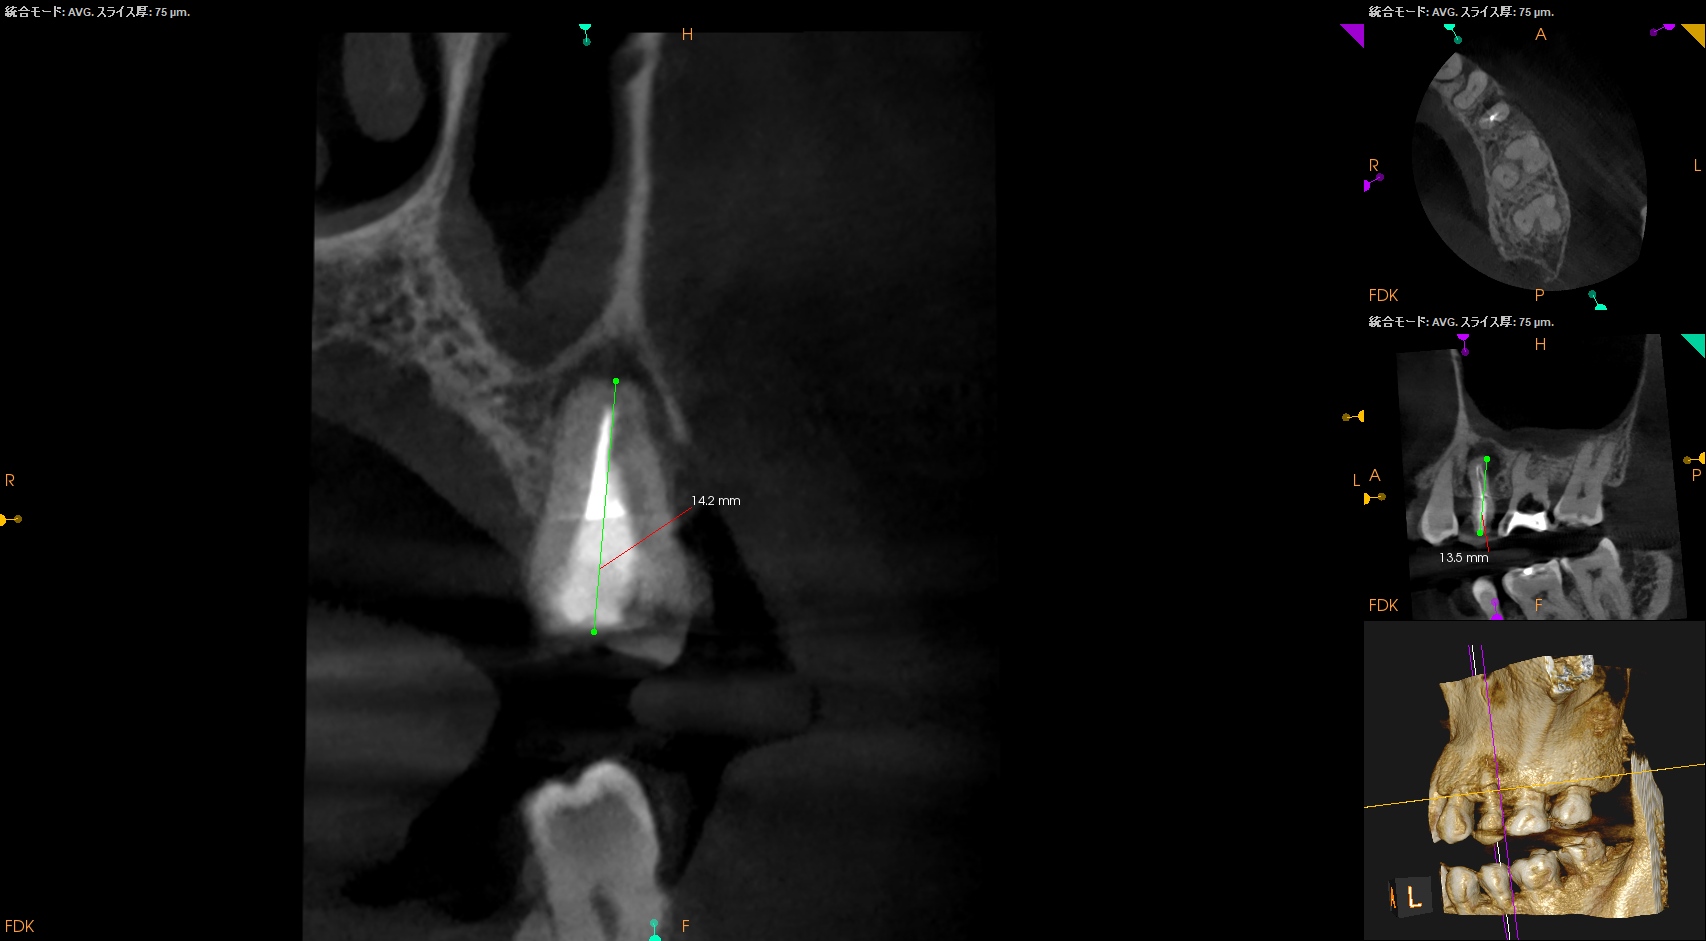

CBCTも撮影した。

これはマストの医療行為である、と私からは告げておこう。

さておき、#13にも病変があるのがわかるので#13も分析した。

#13

#13は#14よりも大きな根尖病変がある。

ここも治療が必要だろう。

Pulp Dx: Previously initiated therapy

Periapical Dx: Symptomatic apical periodontitis

Recomended Tx: Re-RCT

おおよその作業長が類推できる。

が、いずれにしてもこの治療での最大のポイントになるのはMB2がどこにあるか?である。

MB2の根尖部にはCBCTで根尖病変があるからだ。